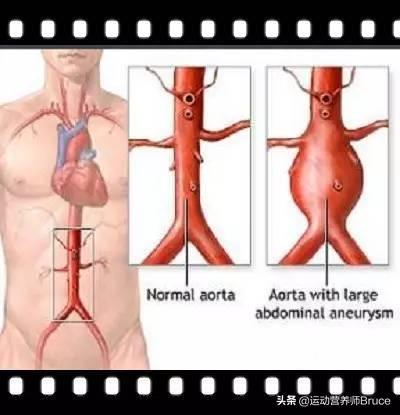

アテローム性動脈硬化症は、成人であれば思春期から誰もが経験する動脈血管の内皮病変である。数十年かけてゆっくりと進行し、最終的にはアテローム性動脈硬化斑を形成して血管を詰まらせたり、破裂させたりして、脳出血、脳梗塞、冠動脈疾患、大動脈瘤の分離などの重篤な心血管・脳血管疾患を引き起こす。

重症化した頸動脈の内膜を切除し、脳梗塞のリスクを軽減できる頸動脈内膜剥離術という方法があります。しかし、手術には一定のリスクがあり、無傷の頸動脈がなくなると術後に血栓症になりやすく、抗血栓療法自体も副作用が多い。ステント留置術、バルーン拡張術、バルーン血栓溶解術など、狭くなった血管を開く医療技術もある。これらの方法はいずれも局所的なもので、症状を治療するものであって根本的な原因を治療するものではなく、本当の意味でプラークを除去するものではない。